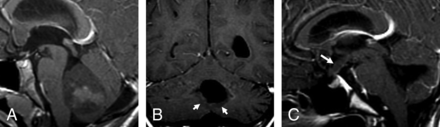

In group 4, of the 14 patients with initial metastasis, 6 (42.9%) showed ependymal metastases with a mismatching pattern (Table 3 and Fig 4A, -B). Four of these 6 patients showed a mismatching metastatic lesion in the ependyma of the third ventricular infundibular recess, a finding that was specific for group 4 (P = .02) (Fig 4C), corresponding to a positive predictive value of 100% for group 4. One group 4 patient (7.1%) showed an ependymal metastasis, which did not restrict or enhance.

Metastatic group 4 tumors. In the first patient (A and B), the ependymal metastases seen in the anterior horns of the lateral ventricles and in the splenium of corpus callosum demonstrate diffusion restriction (B) without enhancement on contrast-enhanced T1 (arrows, B), while the leptomeningeal metastasis seen along the right temporal lobe demonstrates enhancement without appreciable diffusion restriction (arrowheads, B). In the second patient (C), the primary tumor demonstrates minimal enhancement on the contrast-enhanced T1 (arrowheads). The patient has a metastatic tumor in the suprasellar region with 2 components: One is ependymal in the infundibular recess and shows no enhancement (thin arrow), while the second is leptomeningeal and enhances strongly (thick arrow) like other metastasis in the posterior fossa, or supratentorially.

Third ventricular metastases have been known for a long time to occur in medulloblastoma.20 Most reports are case reports published before the era of molecular grouping, some of which were based on CT images, making it difficult to differentiate leptomeningeal from intraventricular masses.21⇓⇓⇓–25 The description of Shelton et al23 resembles what we noted in at least 1 of our patients (Fig 4C): a suprasellar metastasis with an enhancing leptomeningeal component associated and contrasting with a nonenhancing infundibular ependymal component; molecular grouping was not available then. Recently, Nagashima et al25 reported a case of a large suprasellar metastasis from a non-SHH/non-WNT type, without further determination of group 3 or 4. In our series, it was clearly significant that all tumors that presented with a metastasis in the anterior third ventricular infundibulum belonged to group 4 tumors. Besides medulloblastoma, suprasellar, third ventricular seeding is known to occur for high-grade gliomas and pineoblastomas. For some authors, the pattern of “bifocal germinoma” also corresponds to a pattern of metastatic disease spread.26 Therefore, it is not so much the suprasellar/anterior third ventricular location that is surprising in medulloblastoma but that this seemingly occurs in group 4 tumors and not in other groups. Another peculiarity of group 4 metastases is that they enhance in the subarachnoid space but not in the ventricles and that in the ventricles, they may even demonstrate no diffusion restriction. Metastases that do not enhance or show restricted diffusion would be easily missed in the leptomeninges, but not in the ventricles.